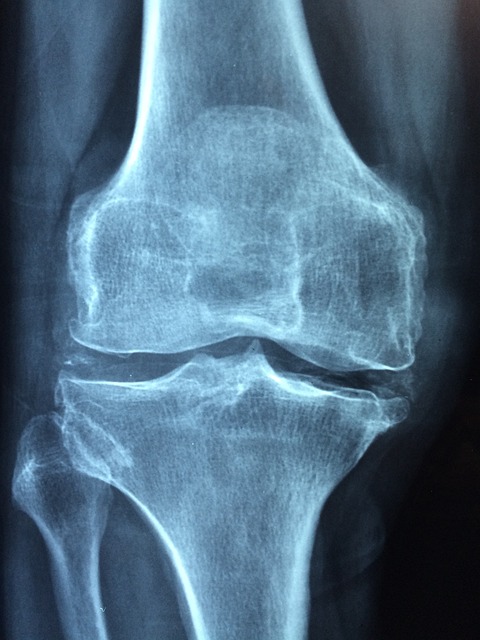

- X-레이: 슬개골과 대퇴골 사이의 정렬 상태를 평가하고, 뼈의 구조적 문제가 있는지 확인합니다. 그러나 X-레이는 연골 자체는 보여주지 않습니다.

- 자기 공명 영상(MRI): MRI는 연골의 상태를 보다 상세하게 평가할 수 있으며, 연골연화증 진단에 특히 유용합니다. 연골의 손상 정도와 연화 상태를 정확히 보여줍니다.